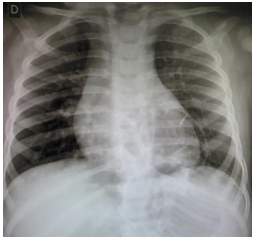

Menina de 1 ano apresenta tosse e coriza nasal hialina há 5 dias, sem febre. Exame físico: bom estado geral, frequência cardíaca de 120 bpm, frequência respiratória de 38 irpm, murmúrios vesiculares presentes e simétricos, com roncos transmitidos de vias aéreas superiores difusos. Antecedentes pessoais: 2 episódios de pneumonias tratadas ambulatorialmente, com 6 meses e 9 meses de idade. Raio x de tórax: imagens a seguir:

Assinale a alternativa que apresenta a principal hipótese diagnóstica.